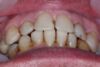

1. Erstuntersuchung

2. Herstellung und Eingliederung eines adjustierten Aufbissbshelfs

Erkennbar ist die massive Abweichung der habituellen Bisslage von der neuromuskulär zentrierten Bisslage.